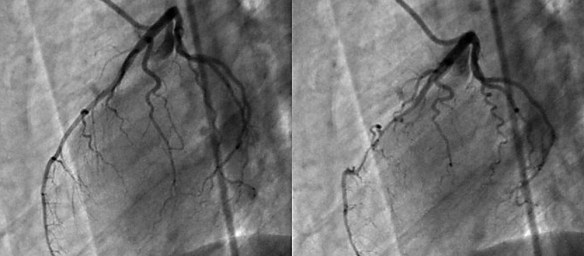

Ecocolordoppler

L’ecocolordoppler è un tipo di ecografia è indicato per lo studio delle strutture vascolari e del loro flusso. Infatti, grazie alla colorazione effettuata mediante calcolatore, si può studiare il movimento e la direzione del flusso sanguigno. Il principio si fonda sulla associazione in tempo reale di una immagine ecografica bidimensionale con un segnale Doppler pulsato. Convenzionalmente, il colore rosso è attribuito alle strutture in avvicinamento alla sonda, mentre il blu per quelle in allontanamento.